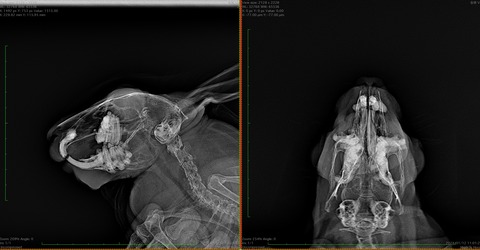

では歯並びが歪んでるとはどういうことかを、レントゲン画像でご紹介します

⇩これが不揃いの子だと

歯根が揃ってないのがわかるかと思います、こういう歯根の子では現状問題なくても膿瘍の発生が警戒されます

健康診断時には歯のレントゲンを撮ってもらっても良いのかもしれませんね

横向けにウサギを寝かせて上からX線を照射し撮影しているので、左右の歯が重なってしまい完璧な評価ができる訳ではないですが、参考にはなります

(理想的にはCTで全ての歯根をチェックするのが望ましい)

歯根の炎症が慢性化すると、歯も変性して濃い白で写ってくるようになります